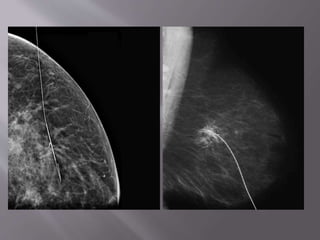

 The best method available to date for preoperative localization of a

non-palpable breast lesion detected on imaging is the hook wire

localization technique described by Frank et al.; 1976

 Studies have shown the importance of supplemental effect of

ultrasound and its ability to detect some lesions missed at

screening mammography

 The procedure of wire localization is achieved with the aid of

ultrasound, as it provides complementary roles to mammography

in the detection of breast masses.